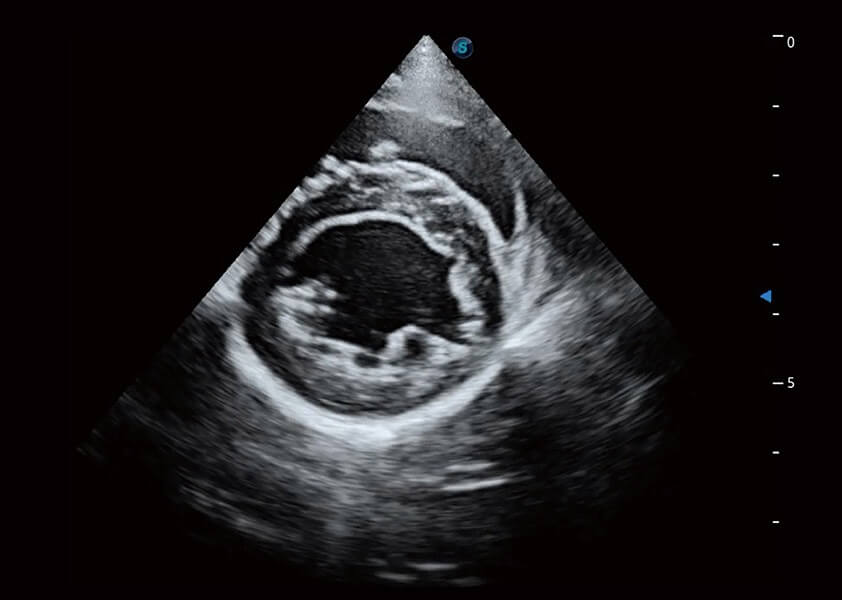

心脏解决方案

ProPet 60 配备了丰富的心脏探头群、先进的成像技术和专业的心脏测量工具,可帮助动物医生为不同体型和生理结构的动物提供心脏和心肌功能的全面评估。

• MQA 心肌定量分析

通过心肌识别技术与二维斑点追踪技术相结合,对心脏的超声图像进行量化分析。计算心肌17个节段的应变、应变率、速度、位移等,并通过牛眼图的形式进行呈现。

• AMM 解剖M型

通过360度任意调节3条M型取样线,在同一心动周期上观察心脏不同位置的运动曲线,得到准确的心功能测量数据,有效评估心肌运动及左心室功能。

优异的基础图像

(犬)乳头肌短轴

(猫)二尖瓣M型